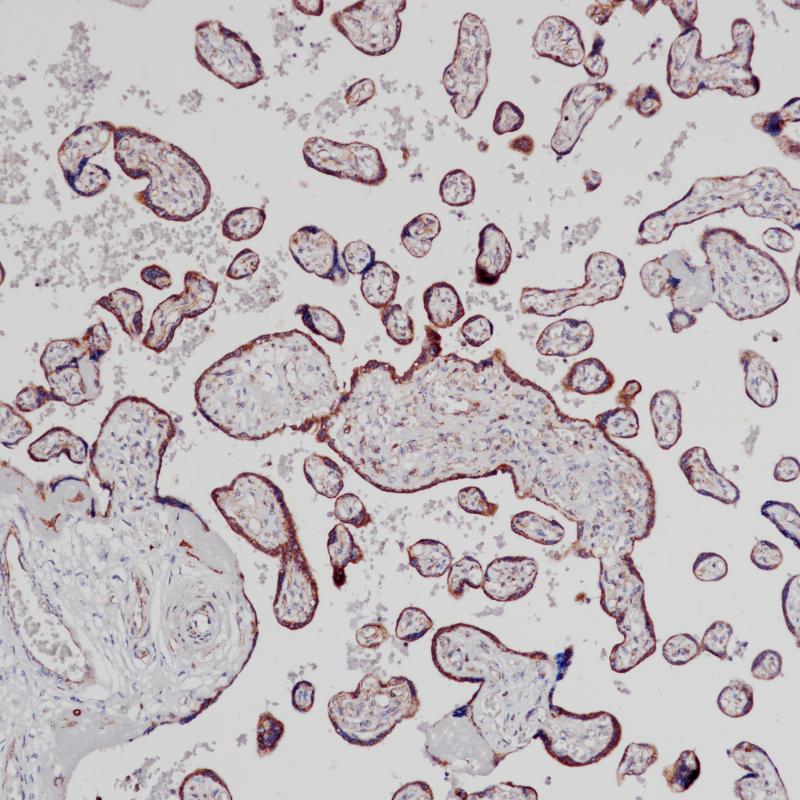

胎盘VEGF(BP6213)染色

血管内皮生长因子A (VEGF-A;原VEGF)属于VEGF/PDGF家族生长因子,在促进血管发育中发挥重要作用。VEGF-A有八个异构体,来自于VEGF-A基因编码的差异剪接mRNA变体。VEGF-A由多种细胞分泌,包括成纤维细胞、巨噬细胞和一些肿瘤细胞。VEGF-A与内皮细胞表面的同源受体(VEGFR2和VEGFR1)结合激活受体并启动下游信号,导致内皮细胞增殖、生存、迁移和血管通透性改变,所有这些都是血管生成的关键过程。